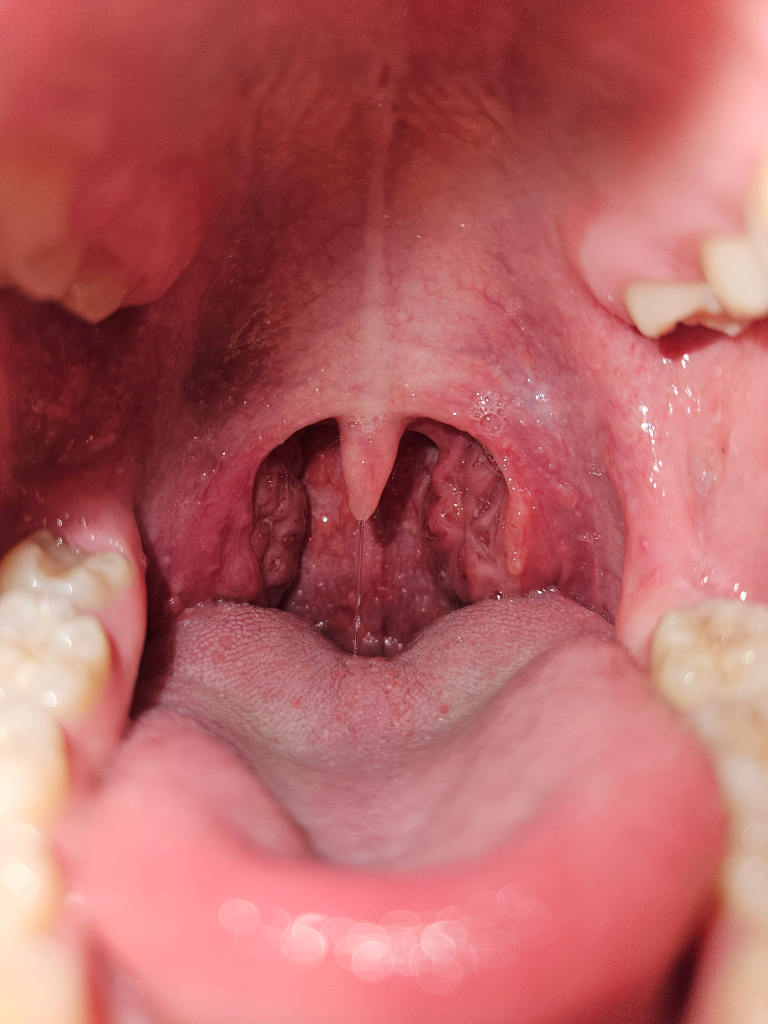

편도염은 편도 주위에 염증이 생기는 것을 말하며, 세균성과 바이러스성 두 가지 유형으로 나뉩니다. 세균성 편도염의 경우, 주로 A군 베타-헤모릴리틱 연쇄상구균이 원인균으로 알려져 있으며, 다음과 같은 증상들이 나타날 수 있습니다:

편도에 고름 또는 백색 점막의 침착

현재 본인의 상태가 열이나 몸살 없이 목이 칼칼하고 반복적으로 통증이 있으며, 병원에서 특별한 염증이 보이지 않았다고 하시면, 바이러스성 편도염이나 다른 비감염성 원인일 가능성이 있습니다. 예를 들어, 만성적인 알레르기 반응, 건조한 환경, 과도한 사용 등으로 인한 목의 통증일 수도 있습니다.